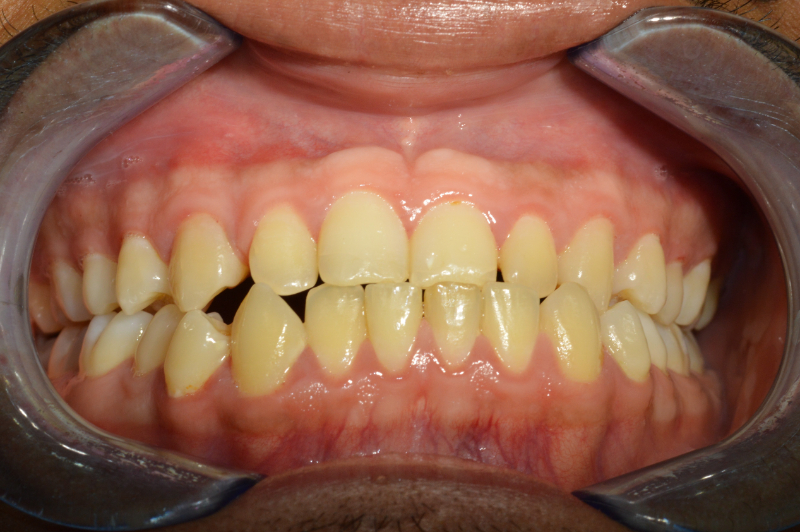

Dopo

Nel 2023 il paziente è stato sottoposto a un intervento chirurgico di avanzamento del mascellare superiore. Lo spostamento delle strutture ossee è stato pianificato virtualmente in fase preoperatoria, utilizzando intraoperativamente un dispositivo di guida (spint/bite) realizzato su misura.

Il decorso post-operatorio è stato regolare: nessuna cicatrice visibile, assenza di deficit della sensibilità e un rapido ritorno alla vita sociale. Il risultato ha avuto un impatto significativo anche dal punto di vista psicologico: il paziente ha ritrovato sicurezza e benessere, grazie al miglioramento dell’armonia estetica e funzionale del volto.

Il trattamento combinato ortodontico-chirurgico ha permesso di correggere in modo efficace la terza classe dento-scheletrica del paziente, con un risultato stabile e armonico sia dal punto di vista funzionale che estetico. L’intervento di avanzamento mascellare, pianificato virtualmente e realizzato senza cicatrici visibili né complicanze sensoriali, ha restituito al paziente un’adeguata occlusione, una maggiore simmetria del profilo facciale e un importante miglioramento della qualità di vita.